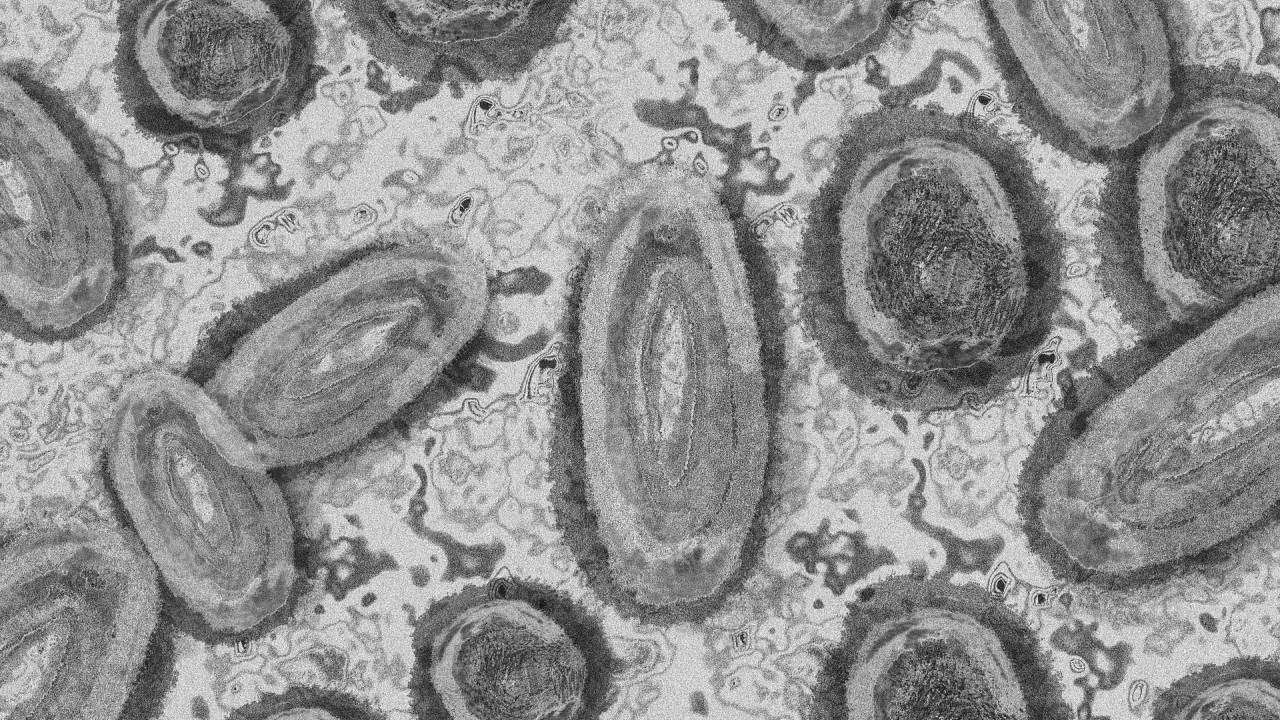

Opičje koze so redka bolezen, ki jo povzroča okužba z virusom opičjih koz. Omenjeni virus spada v rod ortopoksvirusov, ki med drugim vključuje tudi virus variole, ki povzroča črne koze, virus vakcinije, ki se uporablja v cepivu proti črnim kozam in virus kravjih koz.